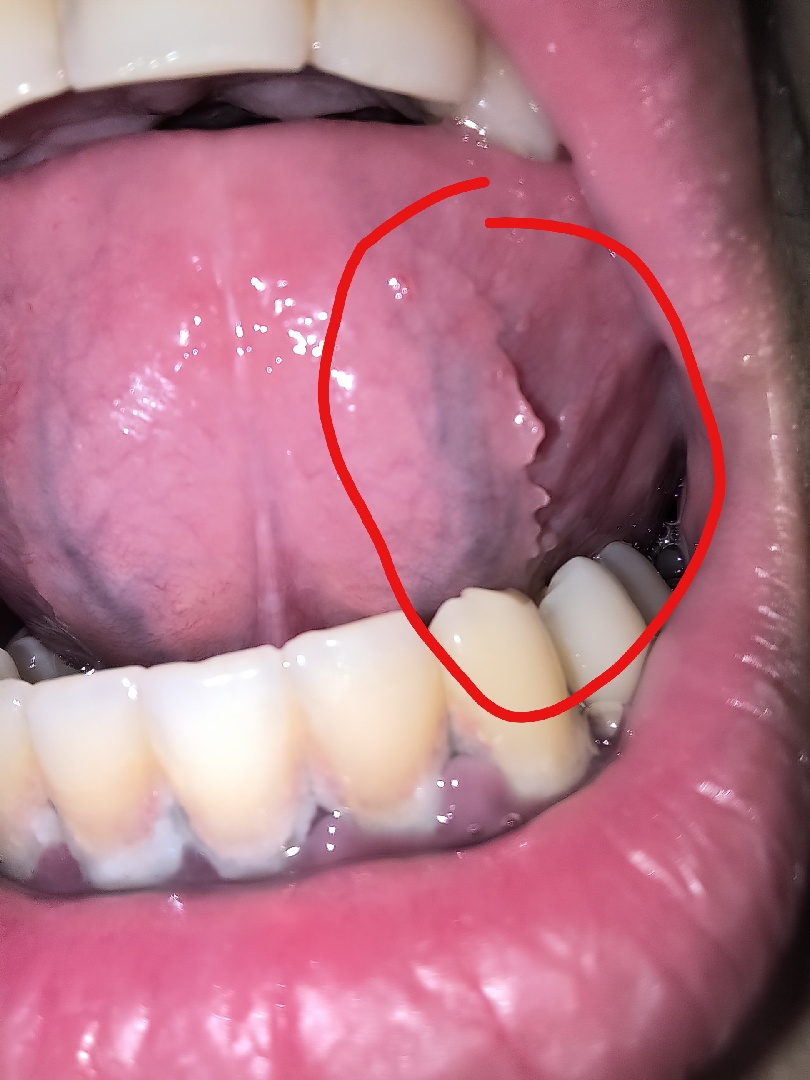

Đây có phải mọc răng khôn không ạ

nó không phải nhiệt miệng có 1 mẩu trắng trắng mọc ra

Cảnh báo: Hình ảnh sau đây có thể gây khó chịu cho một số người xem. Bạn nên cân nhắc trước khi xem.